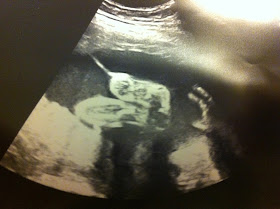

My favorite ultrasound picture of this appointment was Righty's hand and Lefty's feet together: